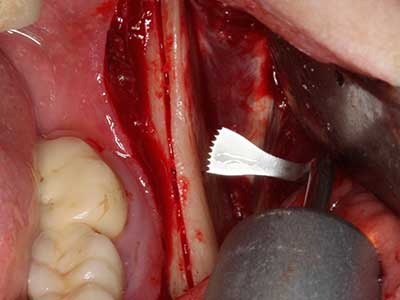

Fig. 3: Basal separation of the block is easier with specially angled attachments.

Fig. 4: Additional autologous bone chips are harvested with the bone scaler.

Fig. 5: Checking the block size at the recipient site.